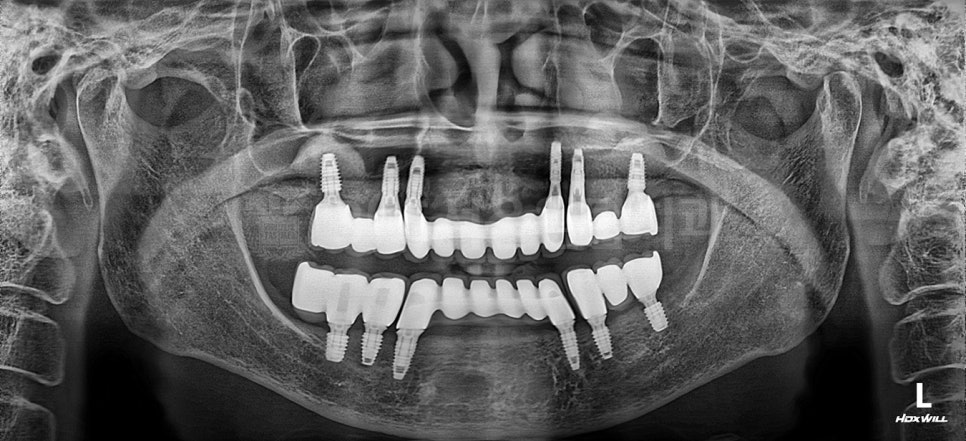

강서구 임플란트 365서울원탑치과의 예시자료입니다.